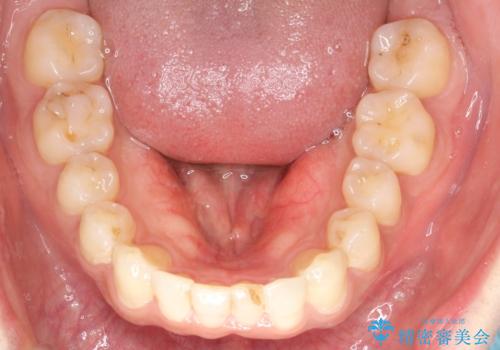

前歯のデコボコした歯並びをマウスピースで改善!

- 前歯の歯並びの改善を希望され来院された患者様です。

初診時の歯並びの状態としては、下顎に中等度のがたつき(叢生)がある状態でした。

抜歯は行わず下顎の奥のスペースを利用して歯をスライドする方法の他に親知らずの抜歯そして上下ともに歯列弓の拡大やディスキング(歯と歯の間の隙間を作る処置)を行い叢生を改善しました。

歯の大きさの不揃いが原因の正中のズレは、ディスキング量を調整することで合わせました。

矯正装置としてはマウスピースを使用しています。

見た目、嚙み合わせ及び、治療期間や施術内容に大変ご満足いただきました。